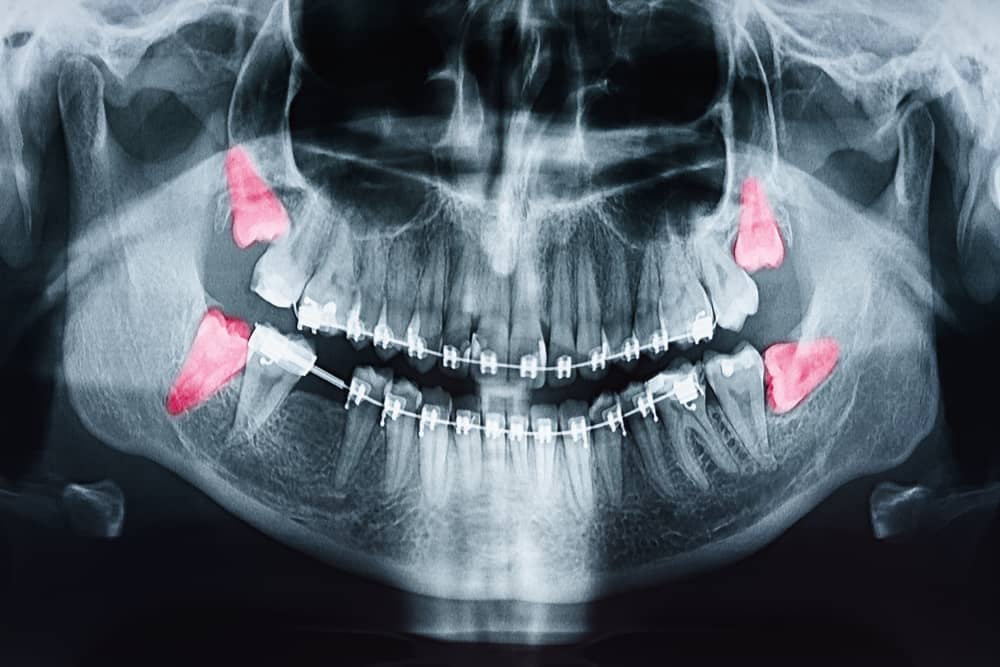

Khám tổng quát tình trạng răng miệng, chụp phim X-quang, tư vấn kế hoạch điều trị

Răng khôn mọc lệch, mọc ngầm

Gây chèn ép, làm xô lệch răng khác

Tạo nang xương, ảnh hưởng đến xương hàm

Chuẩn bị niềng răng hoặc làm phục hình răng